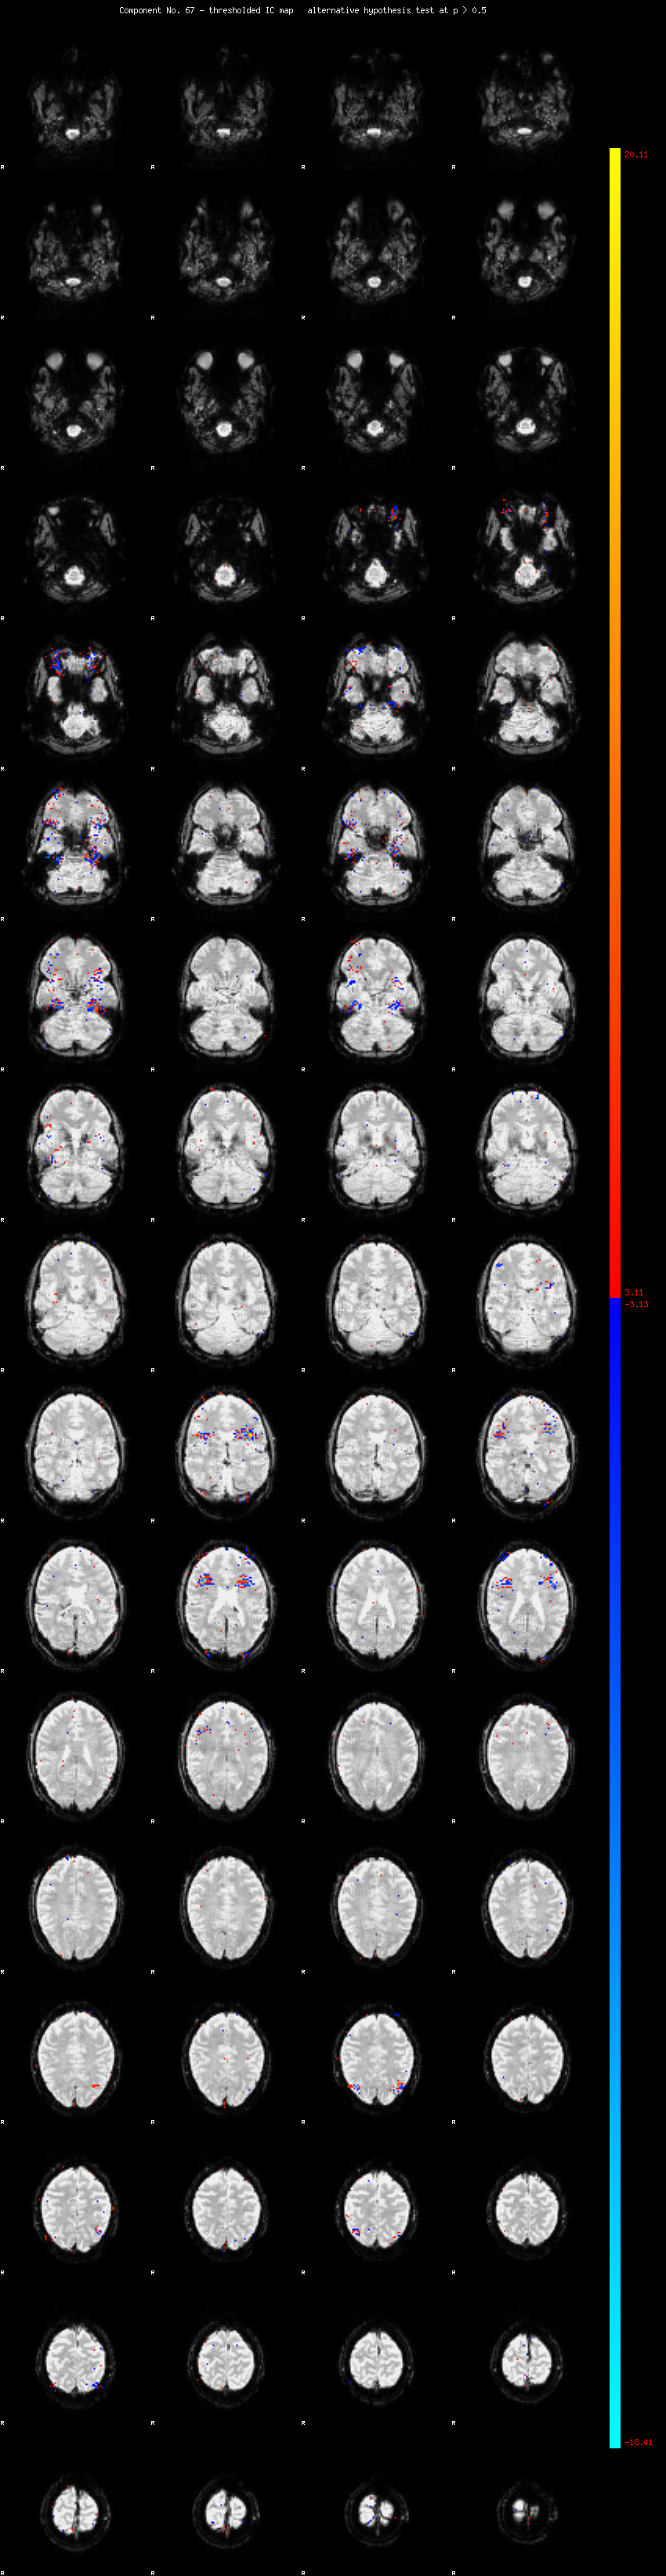

MELODIC Component 67

0.80 % of explained variance;     0.53 % of total variance

MMfit